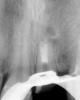

zybnaya feya Опубликовано 29 мая, 2013 Поделиться Опубликовано 29 мая, 2013 (изменено) Всем доброго дня) Давно тут не появлялась,соскучилась за вами всеми и работой Случай мой возможно банальный,но все же Пациентке 3,5 года назад были установлены одиночки е.мах на 11,21,22 Пациентка проходила с ними 3 месяца. Потом произошла травма,треснула коронка 21 . Пац к доктору не обратилась и проходила с трещиной 3 года,пока та не прокрасилась. Может ходила бы еще,но произошла расцементировка СВШ на котором все это добро держалось. Пришлось клеить на жвачку и идти к доктору) Вот такая она ко мне явилась.http://s017.radikal.ru/i410/1305/08/36eecc493b8b.jpg http://s020.radikal.ru/i706/1305/72/f53c6b2073f2.jpg Самая большая сложность состояла в том,что 21 пережил 3 резекции! Длины его корня осталось всего 13мм с диаметром на "апексе" больше 110 Плюс как вы видите пародонтальный карман. Пациентке рассказала о всех подводных камнях.От удаленя она отказалась. Корень неподвижен. Поехали... http://s57.radikal.ru/i156/1305/81/84012f79076d.jpg Апекс закрыт МТА анжелюс который http://s017.radikal.ru/i433/1305/22/07afbb949b4b.jpgНа следующий день проверка мта уз. Все ок. http://s020.radikal.ru/i700/1305/52/1116c7655ba5.jpg http://i011.radikal.ru/1305/e4/d15592222c4f.jpg Снимаем оттиск,бла бла бла... фиксируем ДЦ вкладку http://s47.radikal.ru/i115/1305/13/8d2d0a6f213d.jpg http://s019.radikal.ru/i632/1305/2f/66627a42f173.jpg Времянка (так себе)http://s002.radikal.ru/i197/1305/3c/1fd0205bceb5.jpg После фиксации короночки 21 е.мах http://s48.radikal.ru/i119/1305/10/0efd7e4c8173.jpg http://s018.radikal.ru/i526/1305/0e/836ce54c2334.jpg Соотношение коронка-корень, коропковая-корневая культя конечно критическое. http://s018.radikal.ru/i502/1305/f8/844cedf2543a.jpgДоктор осозает всю тяжесть сиуации,пац нет ,но довольна . Это наверное главное. Хорошо когда люди улыбаютсяhttp://s020.radikal.ru/i723/1305/c0/b4468c881d39.jpg Изменено 29 мая, 2013 пользователем zybnaya feya 9 Ссылка на комментарий